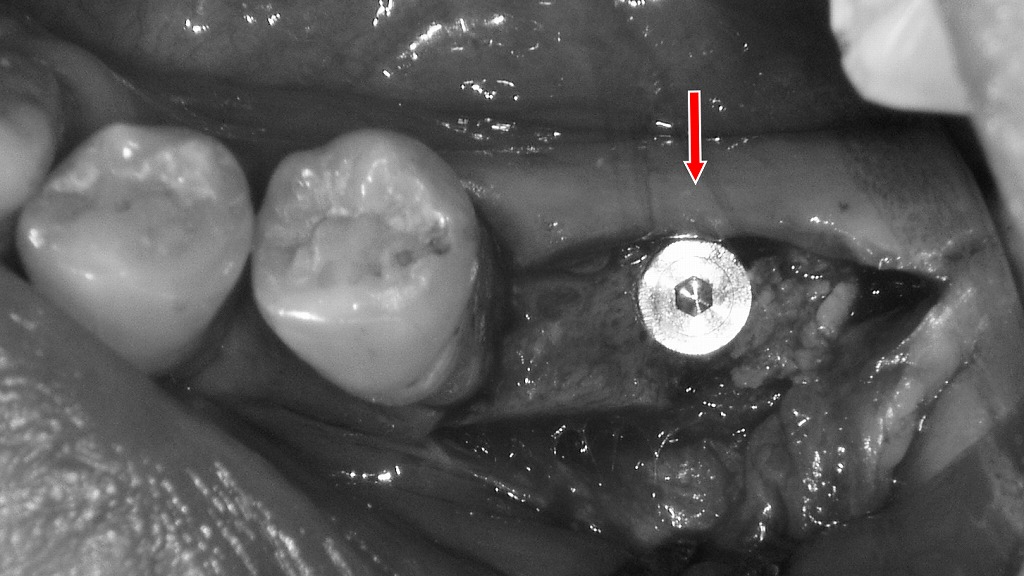

🦷 インプラント治療

抜歯後、人工歯根(インプラント)を埋め込んで噛む力を回復させます。

周囲の歯を削らずに済むため、機能的かつ審美的にも優れた治療法です。

重度の歯周病などにより歯が大きく動揺し、保存が困難と判断された6番を抜歯した症例です。欠損部を放置すると噛み合わせの乱れや周囲歯への負担増加を招くため、抜歯後の治療としてインプラントを選択しました。2枚目の画像は、6番欠損部にインプラント体を埋入した状態を示しています。インプラントは、周囲の健康な歯を削ることなく、歯根の役割を回復し、しっかり噛める機能と咬合の安定を取り戻すことができる治療法です。